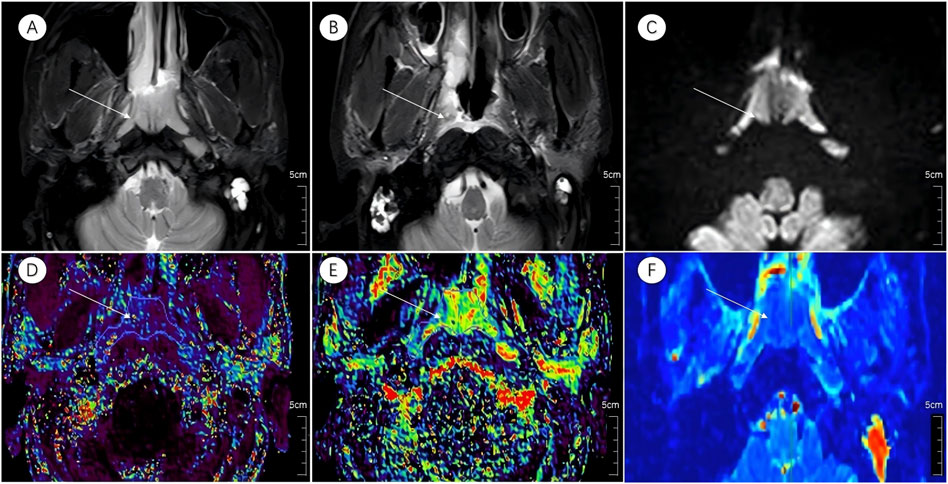

Prior to treatment initiation, the CR group exhibited a markedly lower D than the non-CR group (0.82 ± 0.12 × 10−3 mm2/s vs. 0.92 ± 0.11 × 10−3 mm2/s; t = −2.824, P = 0.007). No significant intergroup differences were detected in the D* or f (P > 0.05 for both). Graphical and tabular data are displayed in Figures 2, 3 and Table 2.

Figure 2

MRI and imaging scans show six panels labeled A to F. Panel A highlights a bright mass with an arrow, indicating an abnormality. Panel B shows a similar scan without the highlighted area. Panel C depicts another view with an arrow pointing to a highlighted area. Panels D, E, and F display colored scans with arrows pointing to different regions, likely showing variations in tissue characteristics or activity. Each image has a 5 cm scale bar for reference.

Figure 2. Multiparametric MR images of a representative patient from the complete response group. White arrows in the figure indicate lesions. (A,B) Axial T2-STIR images obtained before treatment and at the 6-month follow-up after induction chemotherapy (IC) followed by concurrent chemoradiotherapy (CCRT). Image (B) demonstrates near-complete resolution of the primary lesion.(C) IVIM map of the lesion before treatment. (D–F) Parametric maps of Ktrans, Kep, and D obtained before treatment.

3.3 Pre-treatment DCE-MRI parameter comparison

Analysis of DCE-MRI parameters revealed significantly elevated Ktrans and Kep values in the CR group relative to the non-CR group (Ktrans: 0.95 ± 0.34 min-1 vs. 0.30 ± 0.31 min−1, t = 2.557, P = 0.014; Kep: 0.16 ± 0.09 min−1 vs. 0.11 ± 0.06 min−1, t = 2.322, P = 0.025). Ve and Vp showed no significant differences between the two cohorts (P = 0.477 and P = 0.572, respectively). Detailed outcomes are shown in Figures 2, 3 and Table 2.